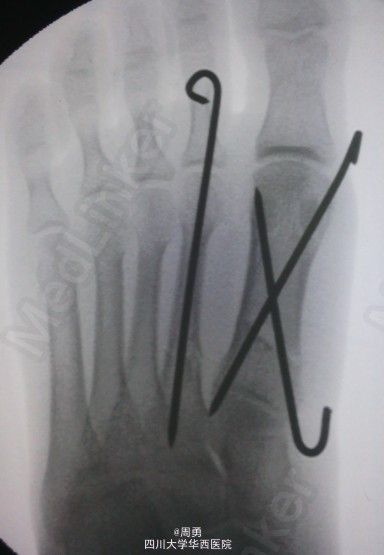

左足第1,2跖骨中近1/3骨折闭合复位克氏针内固定术

此手术为做博士住院总时所做,复位比较满意,价格便宜,效果确实。病例简介:33Y,M,诊断:左足第1,2跖骨中近1/3骨折;处理:行闭合复位克氏针内固定术。